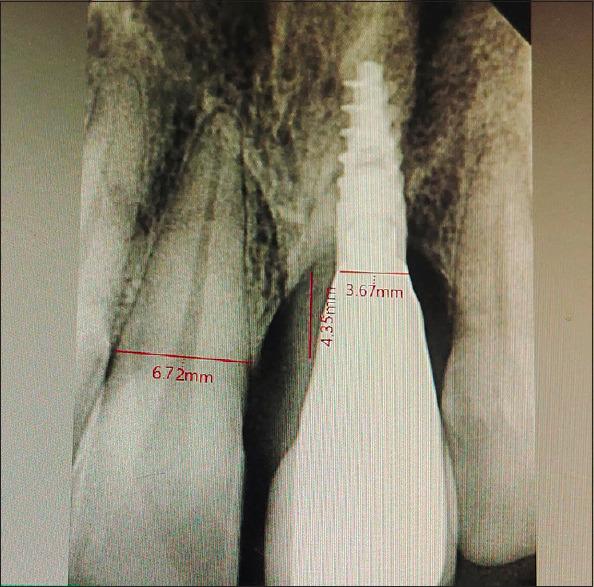

Bone grafting for implant dentistry depends on bone quality, quantity, and biological principles for good outcome. Autogenous bone as donor remains the gold standard among all the available materials. However, it carries unpredictable morbidity and need for different surgical sites. In our report, we describe a simplified approach in bone augmentation for restricted maxillary atrophic defect within the same surgical site as a harvesting site. The method can be an alternative for different intraoral surgical harvesting sites. The patient's left maxillary central incisor before treatment had a large bony defect which was reconstructed though single site approach of augmentation. The implant-supported restoration with healthy periodontium around even after 2 years of review looks promising. The approach can be an alternative for different intraoral surgical sites.

种植牙科的骨移植取决于骨质量、骨量以及实现良好效果的生物学原理。自体骨作为供体在所有可用材料中仍是金标准。然而,它具有不可预测的发病率且需要不同的手术部位。在我们的报告中,我们描述了一种在与采集部位相同的手术部位对上颌局限性萎缩性缺损进行骨增量的简化方法。该方法可作为不同口腔内手术采集部位的替代方法。治疗前患者的左上中切牙有一个大的骨缺损,通过单部位增量方法进行了重建。即使在复查2年后,周围有健康牙周组织的种植体支持修复看起来前景良好。该方法可作为不同口腔内手术部位的替代方法。